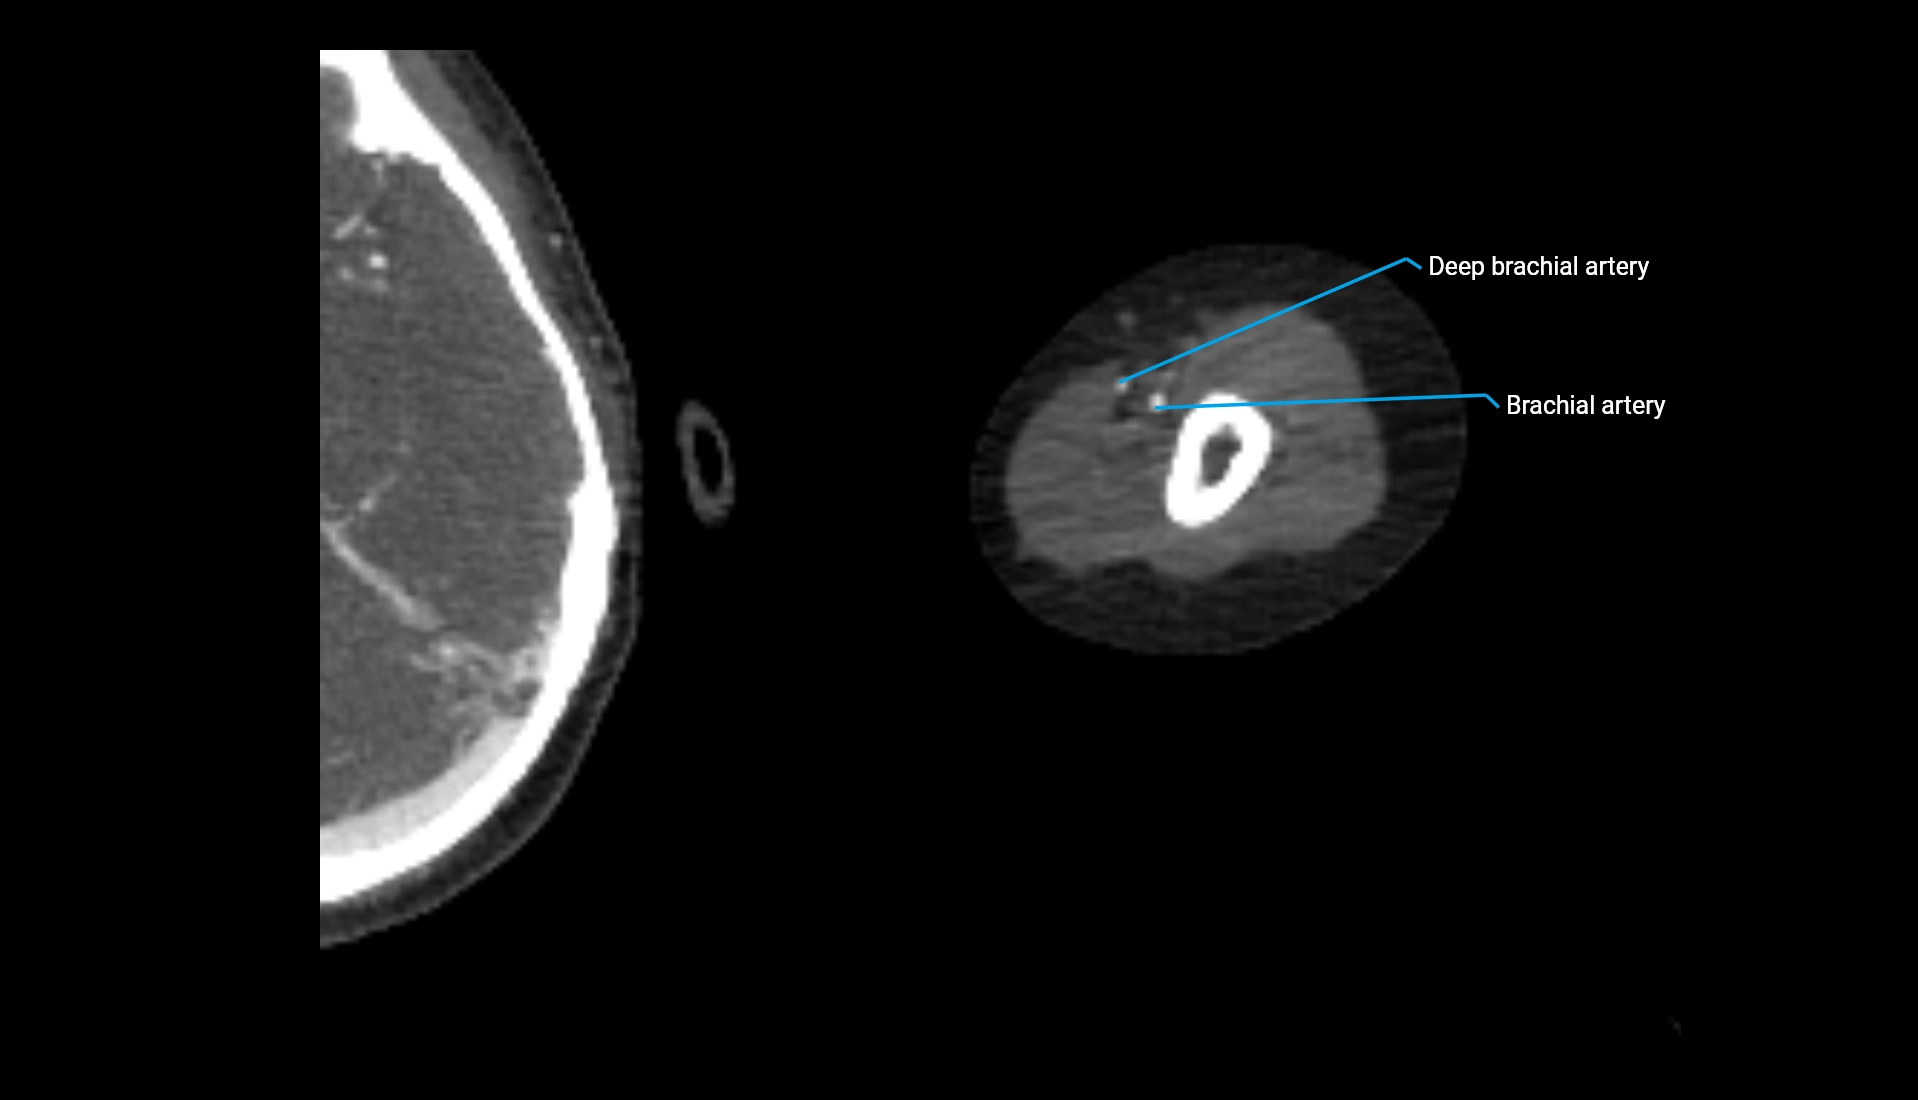

CT Appearance

Non-Contrast CT:

• Cortex: High-density, sharply defined

• Subchondral bone: Dense cancellous matrix

• Articular surface: Smooth concave contour articulating with the capitellum

• Excellent for evaluating bone integrity, alignment, and subtle fractures

Post-Contrast CT:

• Bone: No enhancement

• Joint capsule and synovium: Mild enhancement outlining the joint

• Improves contrast between soft tissues and bony margins

• Useful in detecting subtle joint abnormalities or postoperative changes